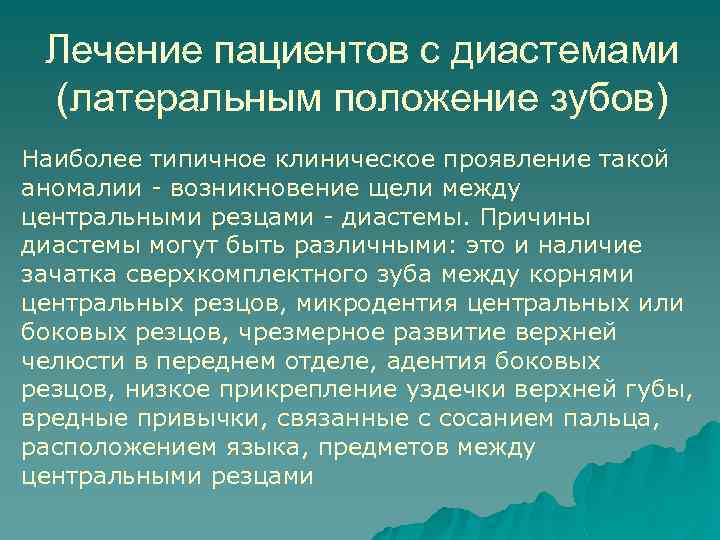

Лечение пациентов с диастемами (латеральным положение зубов) Наиболее типичное клиническое проявление такой аномалии - возникновение щели между центральными резцами - диастемы. Причины диастемы могут быть различными: это и наличие зачатка сверхкомплектного зуба между корнями центральных резцов, микродентия центральных или боковых резцов, чрезмерное развитие верхней челюсти в переднем отделе, адентия боковых резцов, низкое прикрепление уздечки верхней губы, вредные привычки, связанные с сосанием пальца, расположением языка, предметов между центральными резцами